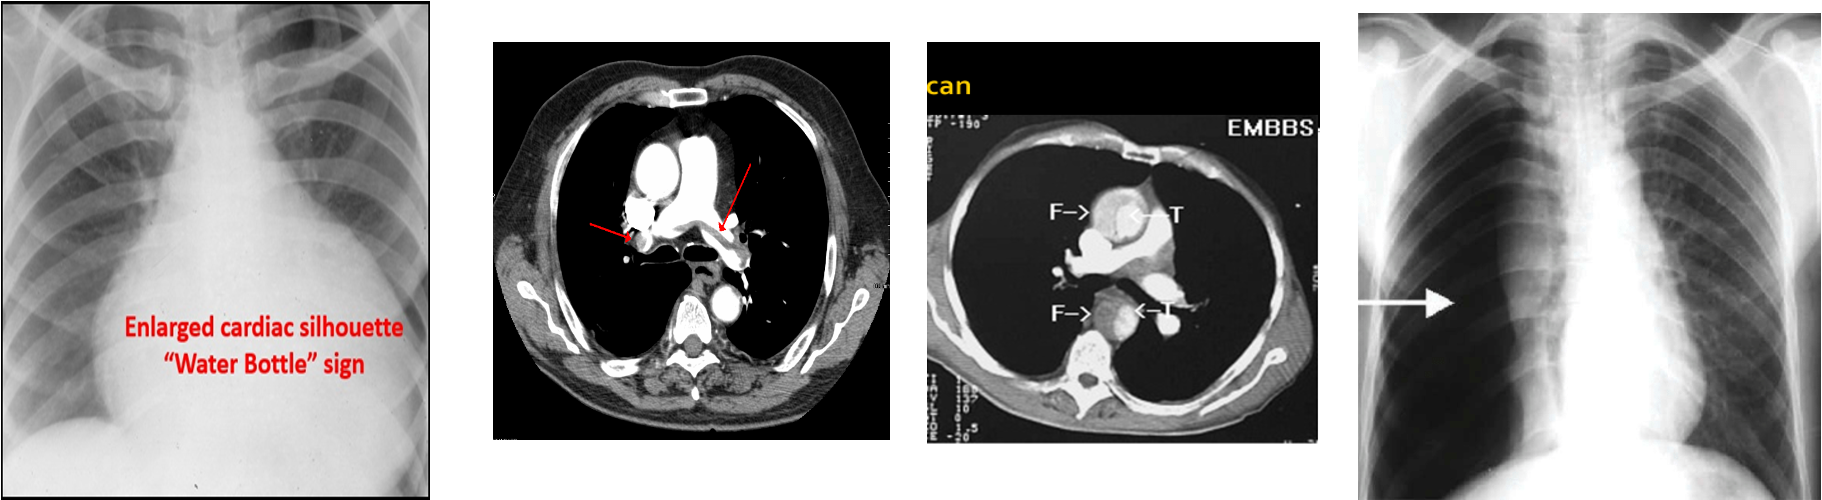

Investigations